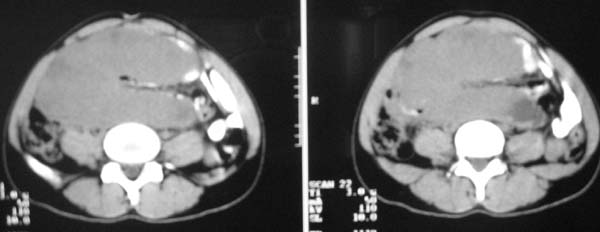

以下是引用zjzjr在2007-9-27 22:20:00的发言:[br]肠腔受推移,未见明显扩张及液平,所以考虑是肠外病灶, 间叶源性肿瘤?脂肪瘤?建议增强。